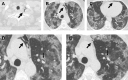

Spontaneous pneumomediastinum is a rare complication of coronavirus disease 2019. The published literature consists mainly of case reports and small case series. There are still many questions regarding the pathogenesis, the prognostic significance and the implications on patient management. In our hospital, 3 coronavirus disease 2019 patients developed spontaneous pneumomediastinum: 1 on admission at the emergency department and the other 2 during hospitalization. In this study we describe their clinical course and computed tomography (CT) findings. All of them had severe disease according to the total severity score on admission CT. The management of pneumomediastinum was conservative and follow-up CT showed resolution in all patients. As the correlation between extension of parenchymal lung lesions and development of pneumomediastinum is still under investigation, we highlight the importance of reporting the severity score on chest CT in order to obtain more comparable results between different studies. Furthermore, in this tragic circumstance we also had the opportunity to familiarize ourselves with the otherwise uncommon occurrence of air along the bronchovascular sheaths (Macklin effect) and evaluate the ability of CT to detect it.